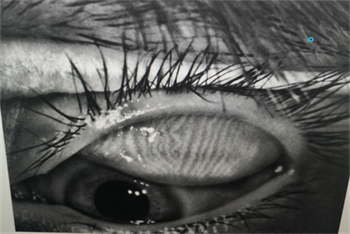

每一個(gè)眼瞼拔3根睫毛,檢查有沒有蠕形螨,以及數(shù)量多少。